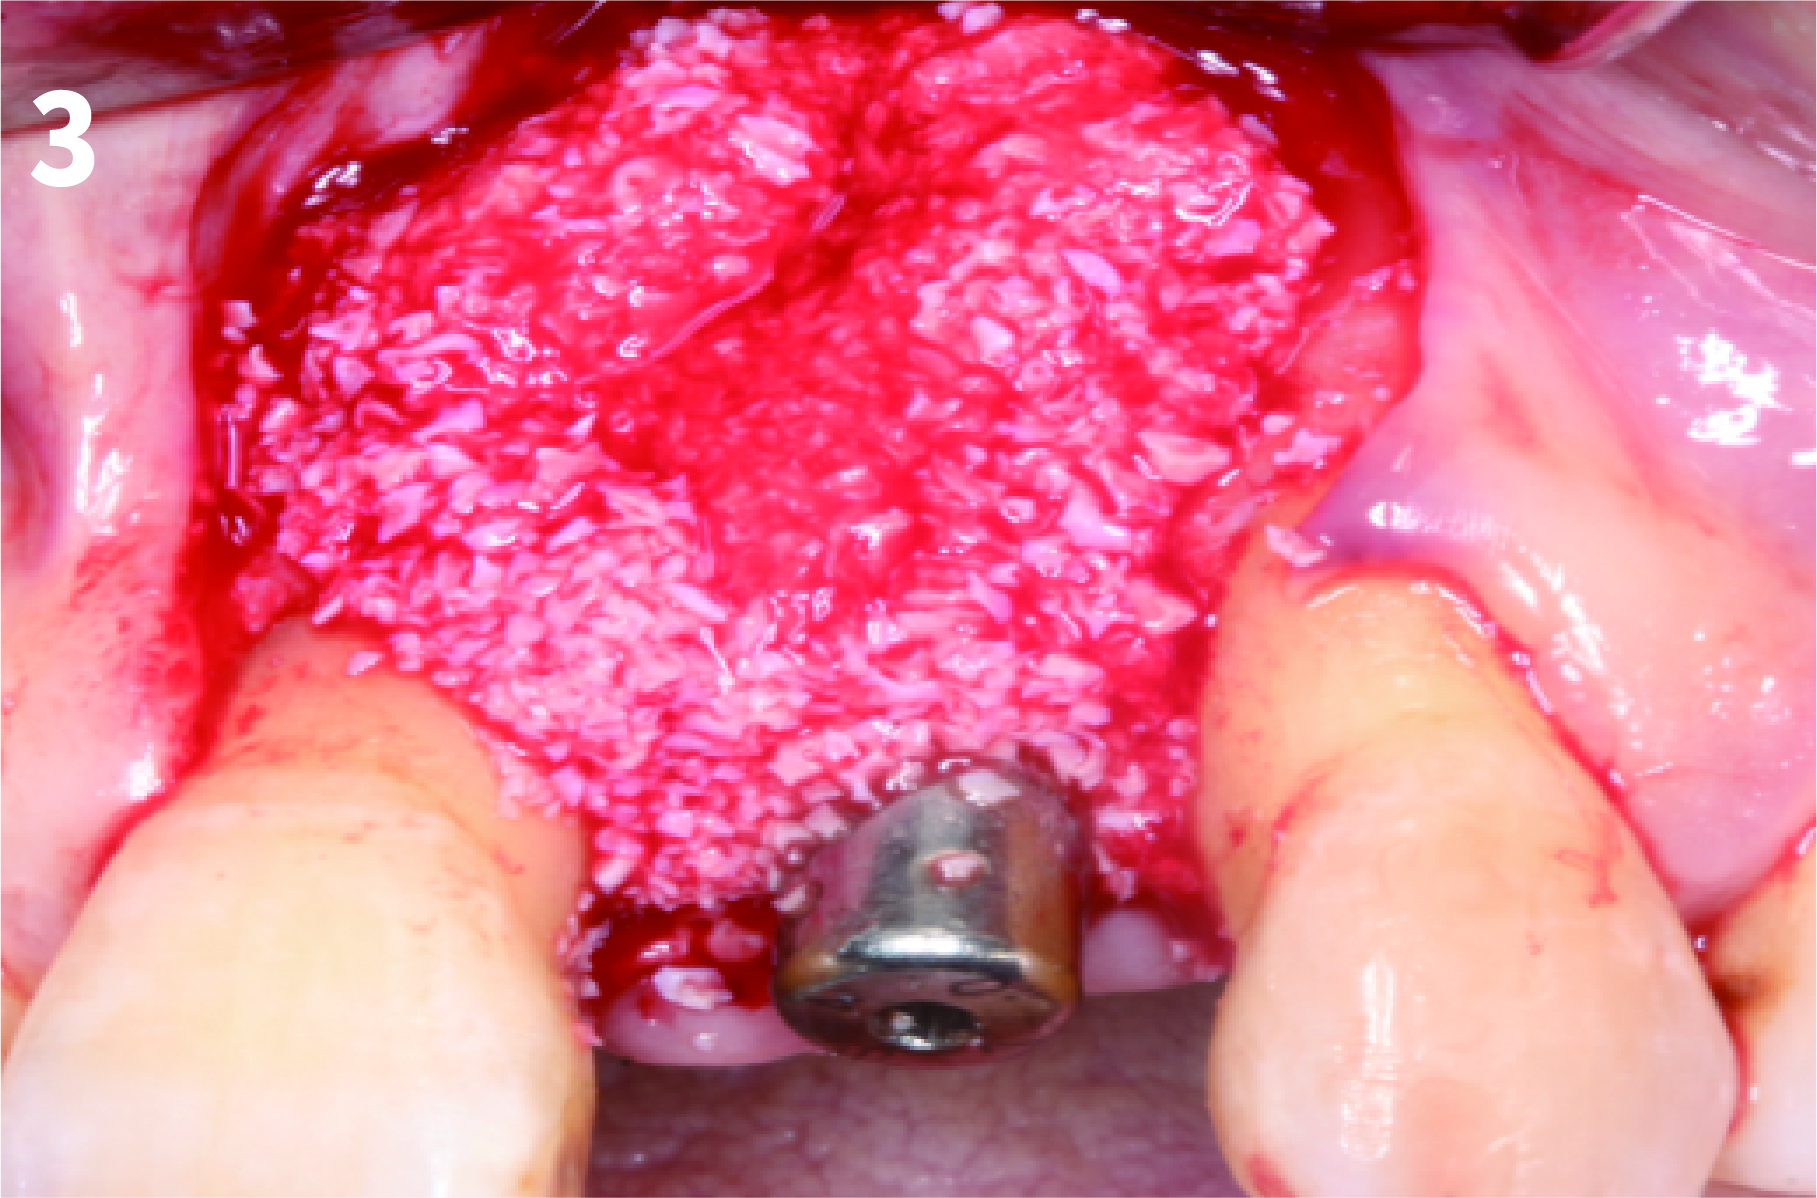

Case 1: Simply Augmented Severe Dehiscence Defect on Anterior Area